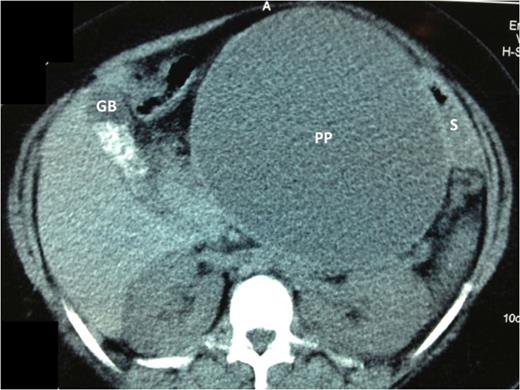

Abdominal ultrasound confirmed cholelithiasis and revealed the presence of a pancreatic pseudocyst containing approximately 1840 mls. A contrast-enhanced CT scan confirmed the presence of a pseudocyst closely related to the stomach (Fig. 1). Endoscopic drainage was not available at our institution. Therefore, the patient was prepared for laparoscopic internal drainage and synchronous cholecystectomy.

Axial cuts of a contrast enhanced CT scan of the abdomen. The large pancreatic pseudocyst (PP) is seen centrally. There is a uni-locular cavity measuring 15 × 17 cm2. The pseudocyst displaces the stomach (S) postero-laterally, but it remains closely applied to the PP wall. The gallbladder (GB) is clearly outlined on these cuts and the gallstones are seen as radio-dense opacities within its lumen.